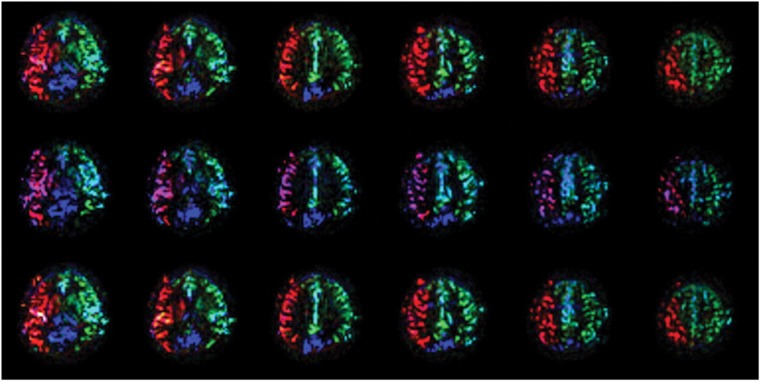

Material and methods: Two healthy volunteers were recruited. Anatomic features and flow directions in the circle of Willis were evaluated with time-of-flight magnetic resonance angiography (MRA) and two-dimensional phase-contrast (2DPC) MRA, respectively. Regional cerebral blood flow was visualized with territorial arterial spin-labeling magnetic resonance imaging (TASL-MRI). TASL-MRI and 2DPC-MRA were performed in three states: at rest, during manual compression of the right carotid artery, and after decompression. In one volunteer, time-space labeling inversion pulse (Time-SLIP) MRA was performed to confirm collateral flow.

Results: During manual carotid compression, in one volunteer, the right thalamus changed to be fed only by the vertebrobasilar system, and the right basal ganglia changed to be fed by the left internal carotid artery. In the other volunteer, the right basal ganglia changed to be fed by the vertebrobasilar system. 2DPC-MRA showed that the flow direction changed in the right A1 segment of the anterior cerebral artery and the right posterior communicating artery. Perfusion patterns and flow directions recovered after decompression. Time-SLIP MRA showed pial vessels and dural collateral circulation when the right carotid artery was manually compressed.

Conclusion: Use of TASL-MRI and 2DPC-MRA was successful for non-invasive visualization of the dynamic changes in regional cerebral blood flow during and after manual carotid compression.